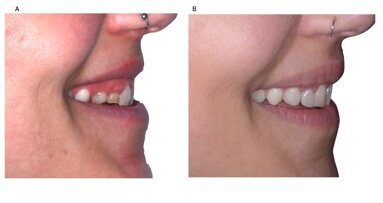

Mediante l’analisi microbiologica è stato possibile osservare che, nel paziente numero uno (Fig. 3) nel tempo intercorso tra il primo prelievo T0 e il secondo prelievo T1, si è verificata una riduzione significativa del Red Complex (Porphyromonas gingivalis, Treponema denticola e Tannerella forsythia), un incremento di Fusobacterium nucleatum, mentre non è stata valutata alcuna variazione riguardante Actinobacillus actinomycetemcomitans. Per quanto riguarda, invece, la variazione a livello parodontale tra T2 e T3, è stata osservata un’ulteriore riduzione del Red Complex, di Fusobacterium nucleatum e Prevotella intermedia; mentre a livello perimplantare, tra T2 e T3, è stato verificato un aumento di tutte le specie batteriche esaminate, con un maggiore incremento per Tannerella forsythia.

Per quanto riguarda, invece, la valutazione parodontale e perimplantare, eseguita mediante i sei denti campione (denti di Ramfjord), ha permesso di osservare un miglioramento di tutti gli indici, soprattutto per quanto riguarda il sanguinamento a livello del dente naturale che si presentava del 2,88% e al termine della terapia del 0,96%; mentre a livello implantare, successivamente all’ultima valutazione eseguita, non è stato riscontrato sanguinamento.

Nonostante il riscontro del miglioramento degli indici, a livello microbiologico, il grafico ha permesso di valutare che il paziente ha presentato una riduzione della flora microbica solo a livello parodontale, mentre a livello perimplantare si è verificato un incremento, questo potrebbe significare che la motivazione sia stata efficace solo in parte oppure che il paziente, pur eseguendo le istruzioni di igiene orale domiciliare, non sia riuscito a metterle in pratica nel modo corretto sulle superfici implantari.